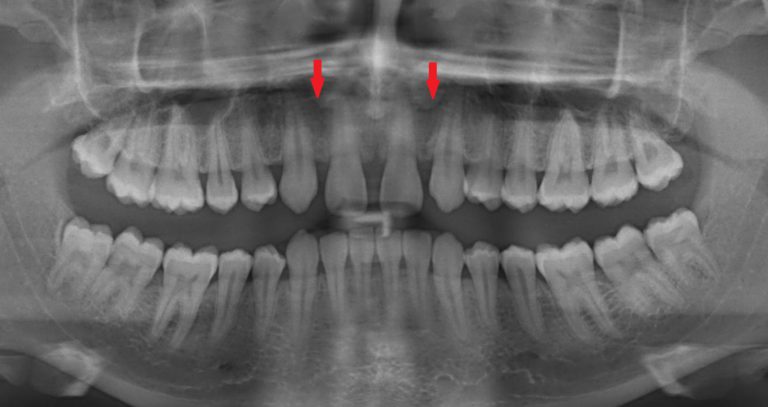

Per “agenesia dentale” si intende la mancanza permanente e definitiva di un dente, sia da latte che permanente. Certamente la causa è dovuta ad un